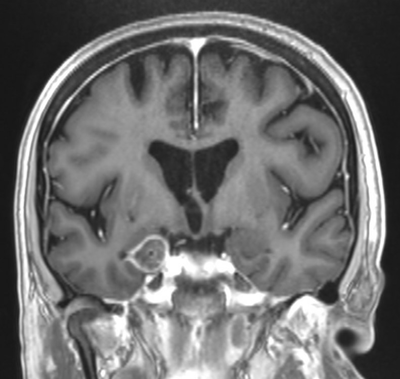

LITT er således et effektivt alternativ til åben resektion ved mindre, eventuelt aflange epileptogene zoner i dybden. For eksempel kan en selektiv hippocampus-ablation opnås ved at indføre kateteret langs hippocampus.

Link: Lægefaglig beskrivelse af hippocampectomi